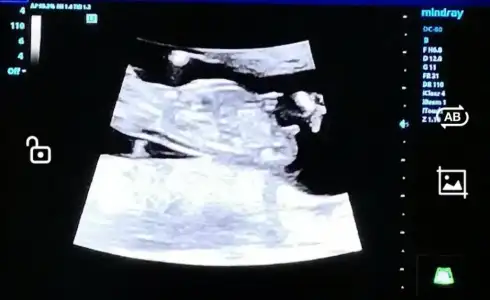

birde en son 19 haftalık olan var bizimde cinsiyet net değil daha ondan merak ettimbaşka foto yok mu burda göbekten aşağı görünmüyor, ayrıca renkli değil de siyah beyaz varsa? 7-8 haftalık hali de varsa onu da yüklerseniz yorum yapabilirim

bu karından mı? karından ise prenses sizi bekliyorbu tek vardı![]()

evet hepsi karından bakalım hayırlısı olsun inşallah 19 haftayı da atayım bi bakınbu karından mı? karından ise prenses sizi bekliyor![]()